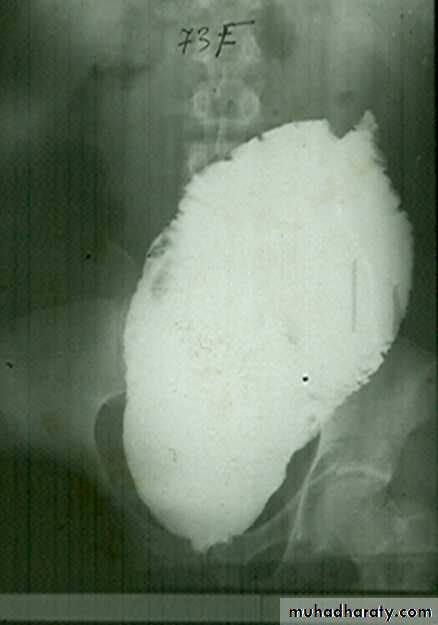

congenital megacolon (Hirschprung disease )

• There is one or more segment of colon devoided from innervation resulting in constriction with proximal dilatation of rest of colon due to weak innervation .• The agangloinic segment usually short , at or near the recto- sigmoid junction .

congenital mega colon

• Rarely the whole colon can be affected result in micro-colon .• 5. Clinically the patient suffering from constipation and abdominal distention since birth .

• 6. The value of Ba Enema is to spot the narrow segment especially prior to surgery .

• 7. Instant Ba Enema is usually done and the Barium used is usually hypertonic .

• Views of particular importance include:

• early filling views that include rectum and sigmoid colon allowing for rectosigmoid ratio to be determined.

• transition zone